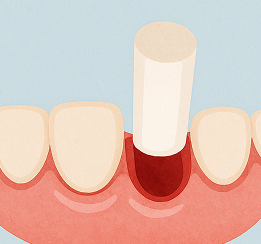

虫歯が進行して神経まで達すると、温かい物がしみたり、何もしなくても痛むことがあります。

歯の神経や感染部分を取り除く根管治療が必要となります。

根管治療後の再発率は約30〜70%といわれています。根管の先端は直径0.25mm程度と非常に細く、精密な処置には専用の機器や設備が欠かせません。

歯のほとんどが失われ、根だけが残っている状態で、神経もすでに死んでおり痛みを感じないです。 抜歯を検討することが一般的ですが、状態によっては歯を残せる可能性もあります。